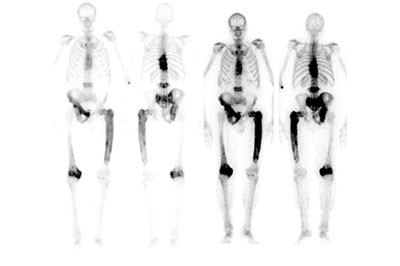

Protocolli terapeutici per morbo di Paget osseo

Sulla base dell’inquadramento diagnostico, formulazione di schemi farmacologici e fisio-chinesi-terapici specifici per morbo di Paget osseo. Monitoraggio delle variazioni metaboliche.

Alcuni test per il morbo di Paget osseo:

- Scintigrafia ossea con tecnezio-99